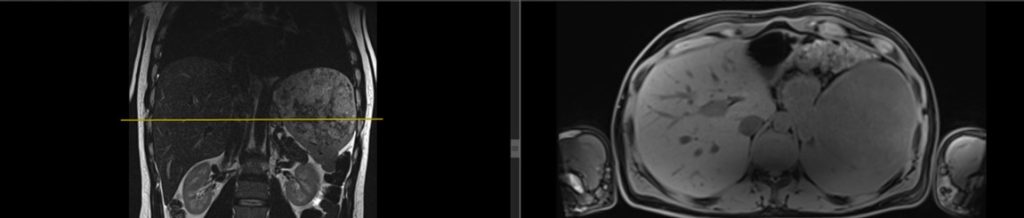

Figura 1: imagini în plan coronal și axial în ponderatie T2 din achiziție IRM abominală superioară cu substanță de contrast